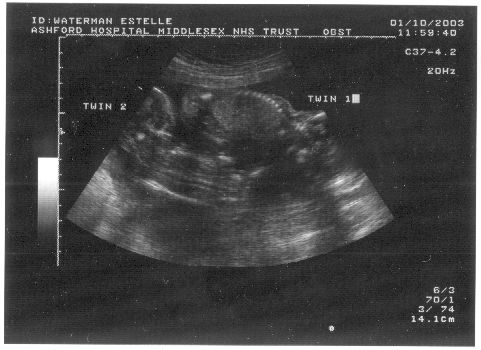

16 week scan

It gets better at the 16 week scan. The twins are growing very

nicely indeed. The below section of notes shows that both babies are

above average size on the scale, with one off the scale! At the

moment we've renamed them "big and bigger".

16 week Notes:

16 week babies: